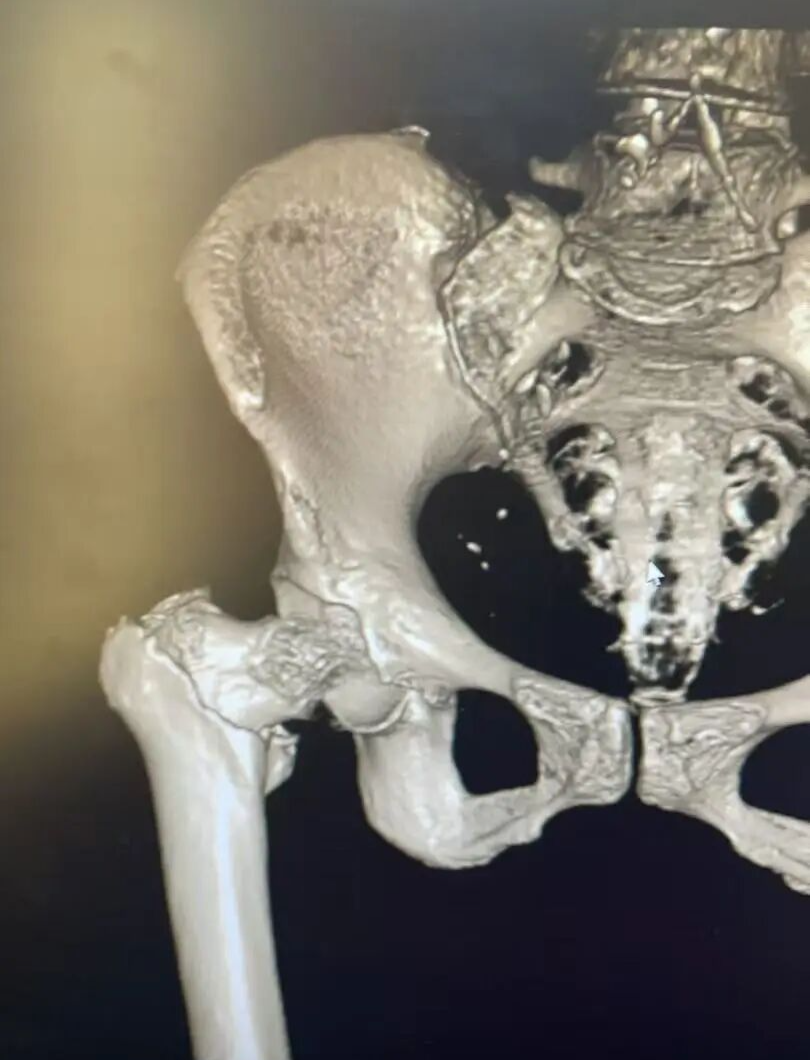

患者术后影像

手术过程顺利,术后 复查DR ,显示 断端对位良好,金属内固定在位, 手术效果满意。